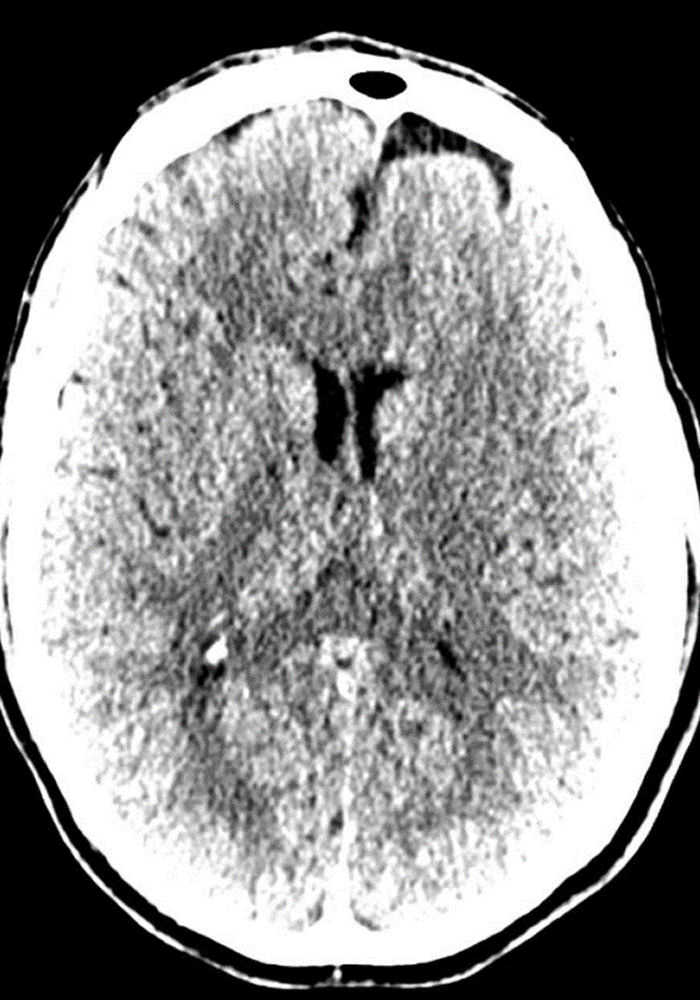

Before: "fuzzy" head CT

datascientists after

After: detailed images

Our V Star computer scientists wrote a module for 3D-Slicer allowing careful alignment and summation from 8 prior CT scans obtained over a course of several years. This improved image contrast resolution without loss of spatial resolution